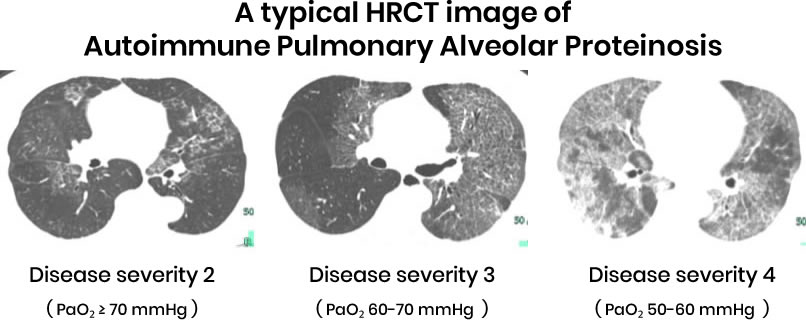

1. Chest X-ray or CT Scan?

- Shows “crazy paving” pattern, indicating lung abnormalities.